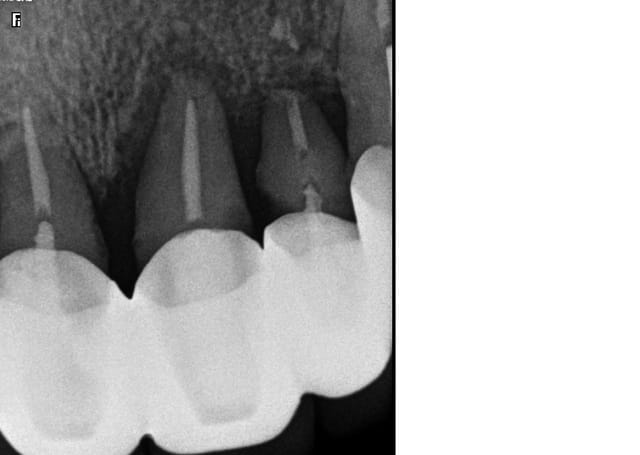

Ra 21 22 23 l7mv66 - Eugenol